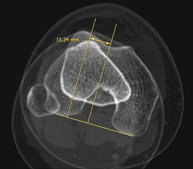

Lower leg rotational study using CT [patella, tibial tuberosity to trochlear groove (TT-TG) distance]

Radiological examination based on an X-ray system and detectors that rotate around the patient, reconstructing the images by computer (multidetector computed tomography - MDCT) to calculate a series of measurements at the hips, knees and ankles with a view to solving problems affecting the rotation and angulation of the lower limbs.